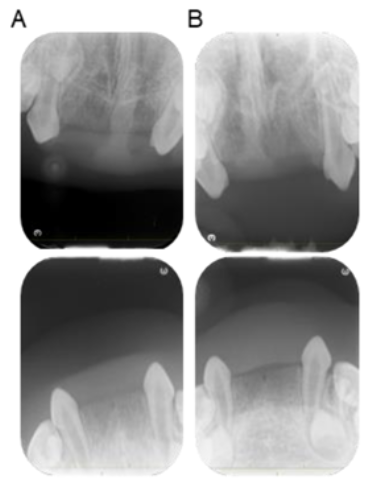

2. Case Presentation